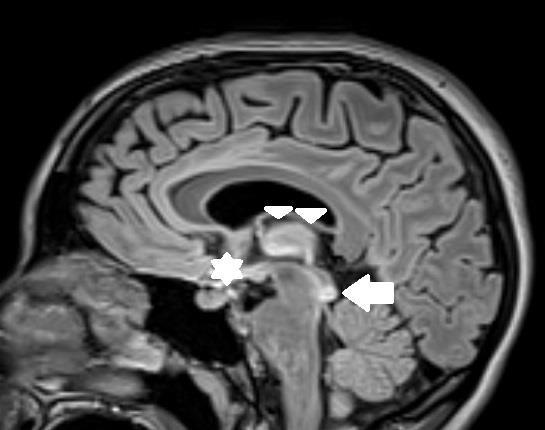

349 Acute Cerebellar Infarct in A Patient with Undiagnosed Fahr’s Syndrome: A Case Report

RW Slaven, M Huecker, D Kersting

377 Undiagnosed Schizencephaly Presenting as Breakthrough Seizures

J Coacci, P Viccellio